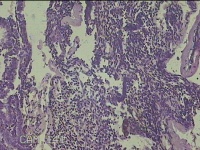

宫腔内容物

性别

女

年龄

45岁

临床诊断

子宫内膜息肉

一般病史

月经量增多10年,B超检查发现宫腔异常回声半月余。

标本名称

大体所见

灰白暗红色不规则碎组织1.5x1.3x0.7cm一堆。

图1